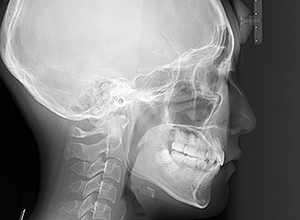

| X-Ray所見 | |

| セファロ所見 | 下顎頭はやや後方に位置しているが骨体部、下顎枝共に大きく上部構造体に対してバランスよく位置付いていた。中顔面は奥行きがあり下顔面高の高さは高くなかった。 |

| 批評・予后 | 治療後において閉唇時の頤筋の過緊張の改善及び咬合の緊密化と歯根のパラレリングが認められ、良好な咬合が確立できたと思う。 現在は保定をしつつ下顎両側第三大臼歯抜歯の抜歯を検討している。 |